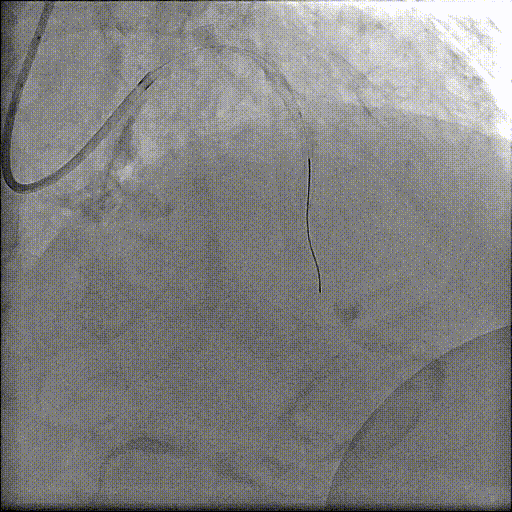

术中,杨征手术团队首先处理冠状动脉问题。造影结果显示,患者的冠脉血管不仅堵塞严重,而且钙化非常坚硬,常规器械难以通过。团队立即采用冠脉内旋磨技术,根据病变特殊性,选择高速旋转的「偏心」旋磨头对钙化部位进行处理。

与传统的同心旋磨不同,偏心旋磨系统的磨头质心与旋转轴线不重合。这种设计使得旋磨头在自转的同时,还能沿血管内壁进行公转扩径运动,扩大治疗范围,降低手术风险。尤其适用于处理过去难以治疗的血管转弯处的重度偏心型钙化斑块,能让支架得到完全扩张,减少残余狭窄。

完成血管的旋磨处理后,精准地释放了支架,冠脉血流瞬间通畅。手术团队则立即转向主动脉瓣置换。